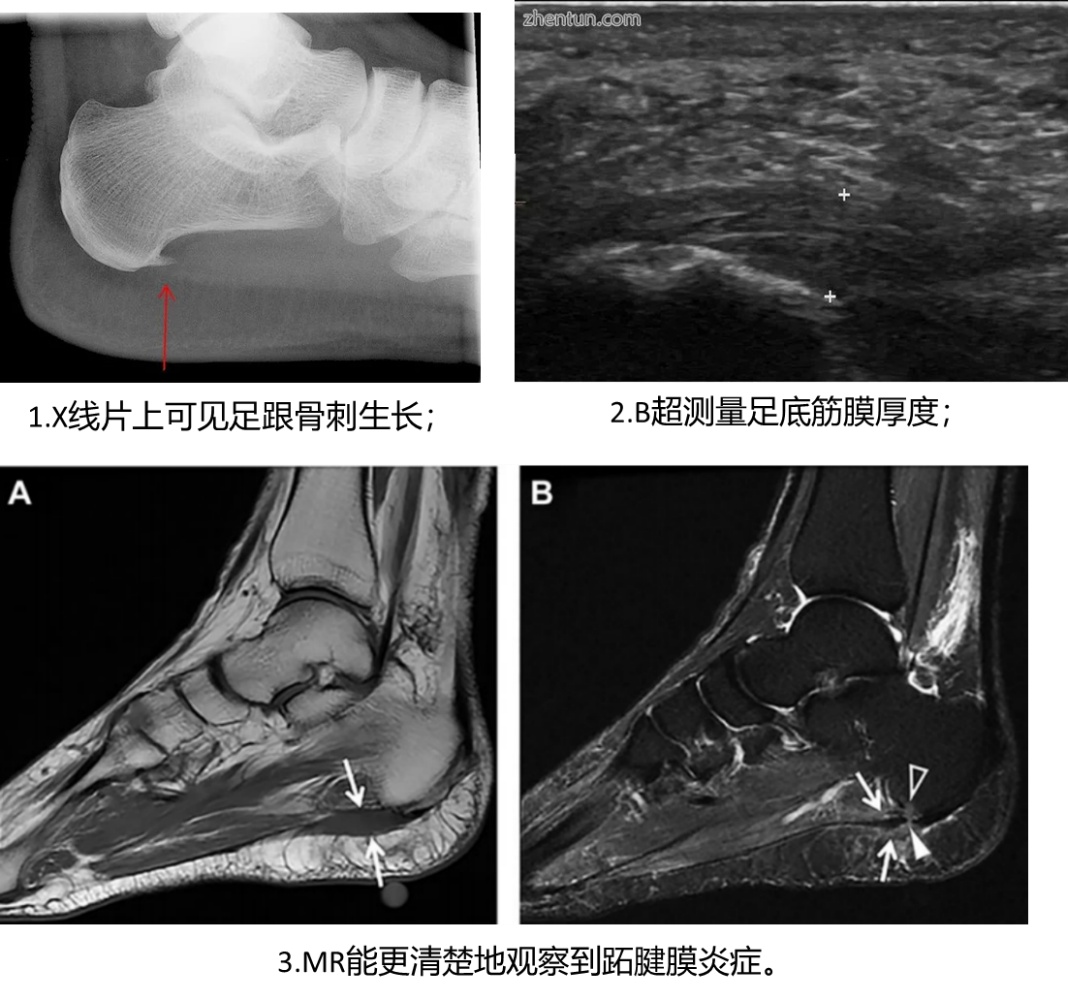

此外,辅助检查有助于进一步明确足底筋膜炎的疼痛点,并有助于与其他全身性疾病引起的足底疾病鉴别。常见的检查方式有X片、B超、足部MR等,提示患者足部的骨刺增生、筋膜增厚或炎症等。